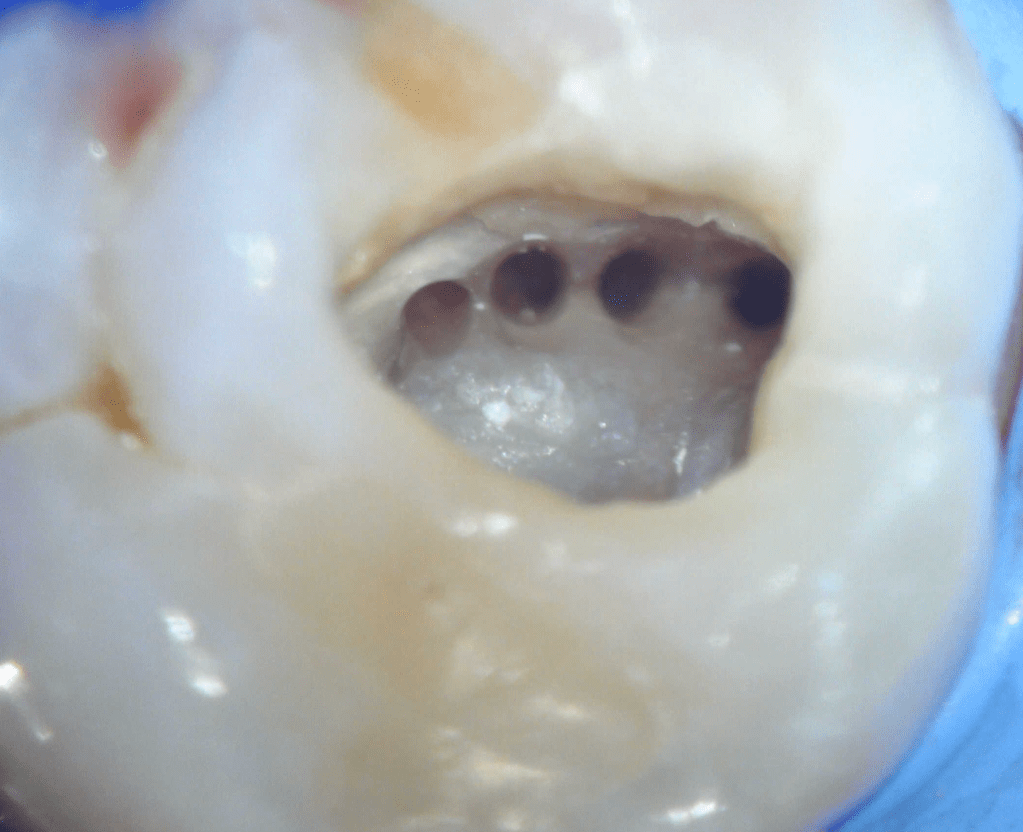

Reco preendo + 4 conductos molar superior